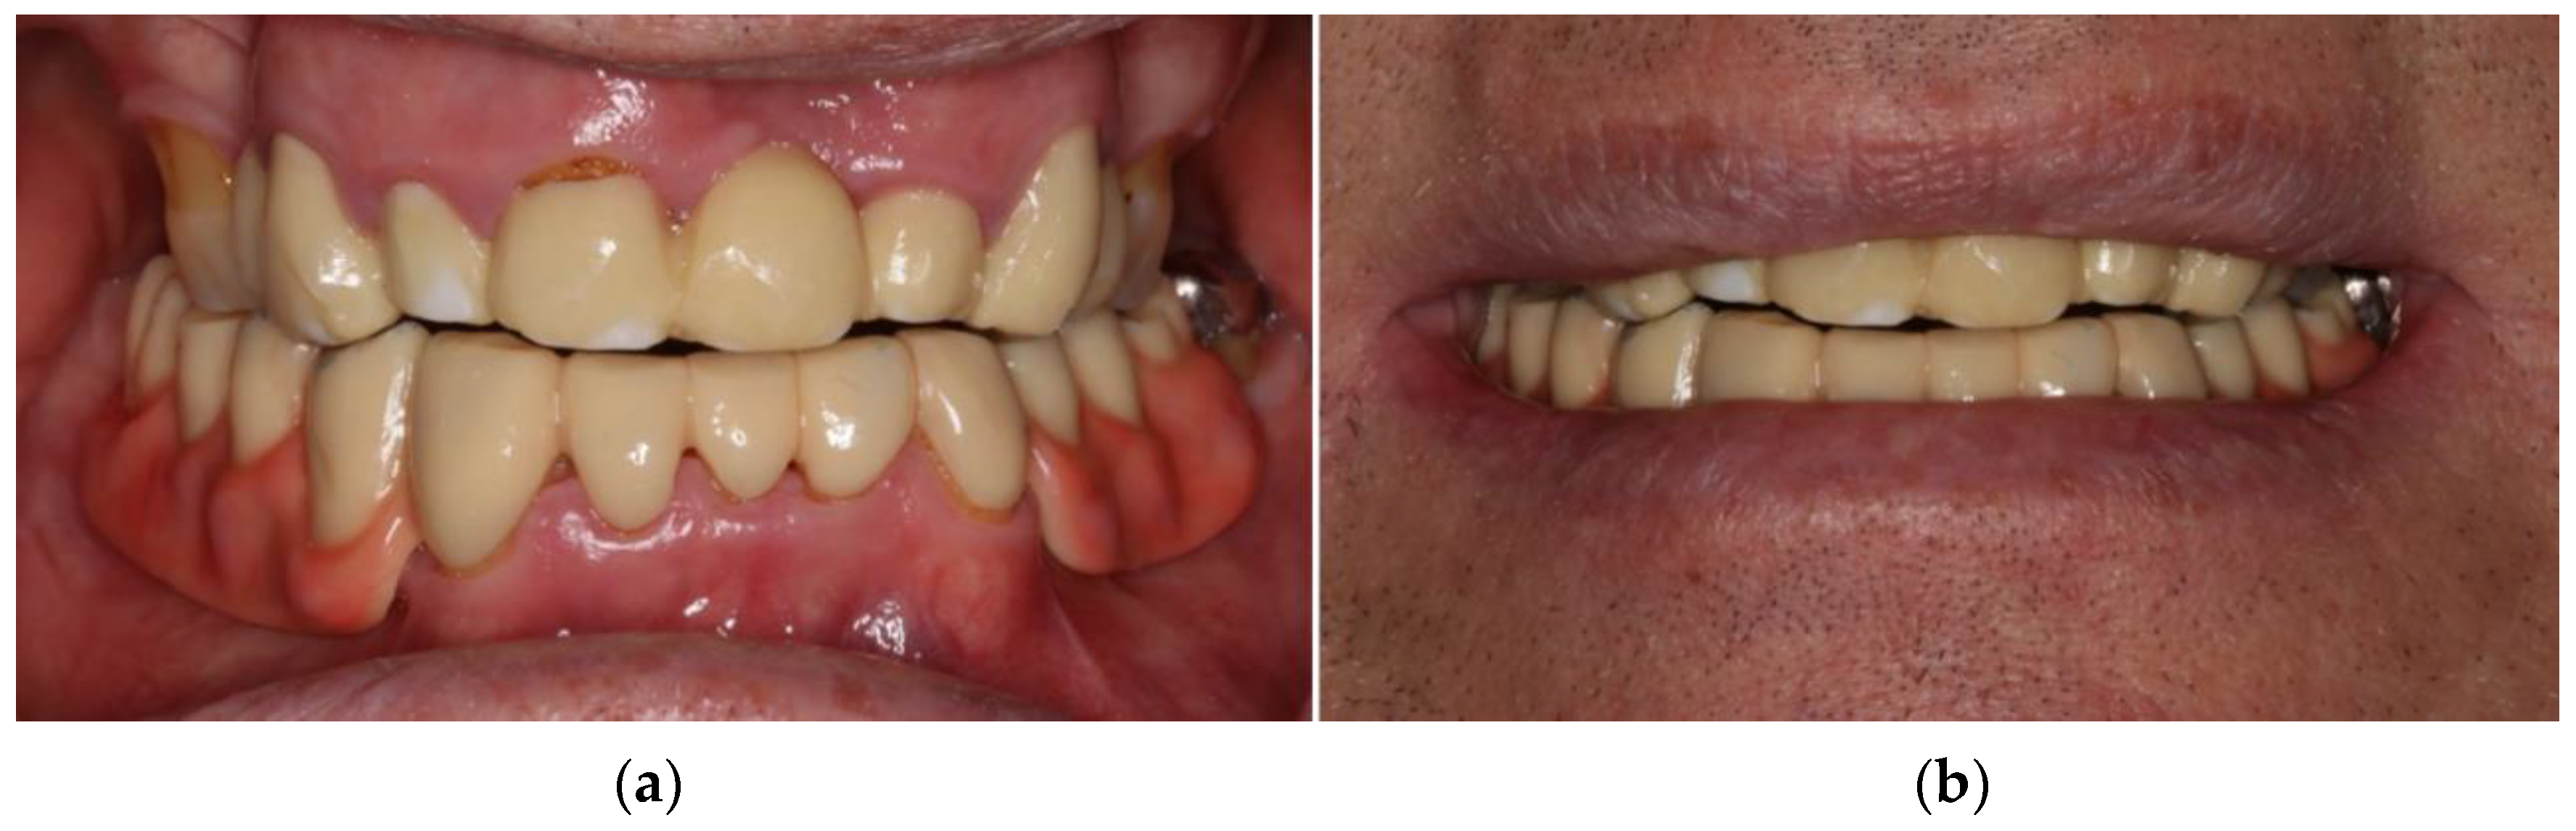

3. Case Report

- Locator abutments on both implants, single-crown FDPs on the remaining lower molar teeth, insertion of a tooth-colored and tooth-shaped monolithic RDP fabricated from POM with minimally invasive preparation of the lower anterior teeth (experimental character in long-term endurance).